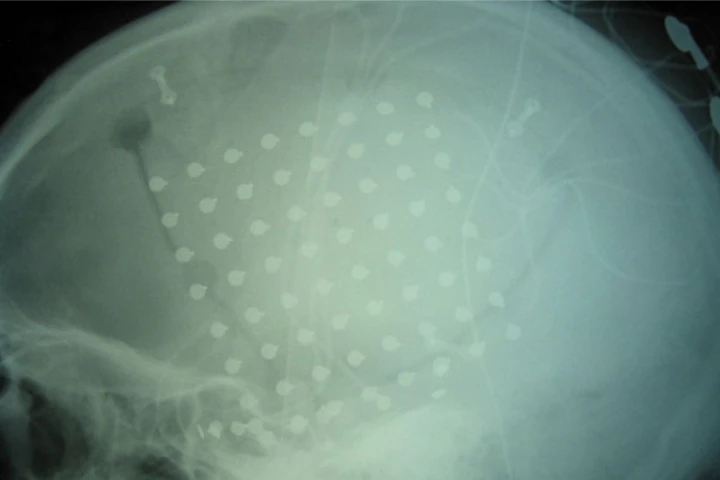

When it comes to accurately reading the brain's electrical signals, many systems utilize implantable electrodes. A new technology is reportedly less invasive yet just as accurate, as it swaps regular electrodes for ultra-thin wires.